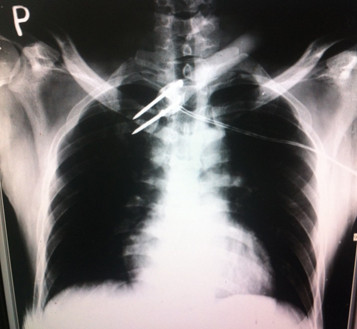

Bác sĩ Hiệp cho biết, dị vật cắm sâu vào thành ngực ở vũng hõm ức lệch phải. “Lần đầu tiên tôi mới thấy dị vật này. Qua phim X-quang, phần ngập trong ngực bệnh nhân có hình như mũi tên với 2 mũi kim loại nhọn dài khoảng 3cm, có thể được tự chế từ căm xe. Phần kim loại này được gắn vào cán gỗ dài. Một trong 2 mũi nhọn còn ”, ông nói.

Phim X-quang chụp vùng ngực bệnh nhân cho thấy mũi tên điện có 1 dây diện nối vào phần mũi nhọn kim loại. Ảnh: Quốc Ngọc